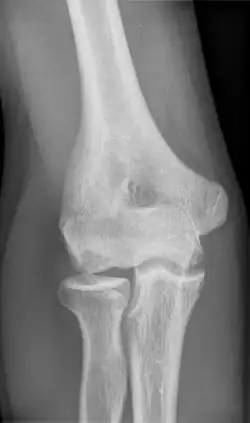

Unter Morbus Panner (juvenile Osteochondrose des Capitulum humeri, Panner-Krankheit) versteht man eine Knochennekrose des Ellenbogengelenks. Diese tritt vor allem bei Kindern und Jugendlichen auf.

In der bildgebenden Diagnostik (Röntgen, Computertomographie, Magnetresonanztomographie) können vier Stadien unterschieden werden:

- Stadium I: Subchondral betonte Verdichtungen des Knochens (Sklerose)

- Stadium II: Auflockerung der gelenkflächennahen Binnenstrukturen (Fragmentation)

- Stadium III: Knöcherne Destruktion mit Größenreduktion der Epiphyse (Osteolyse)

- Stadium IV: Regeneration der Epiphyse (Reparation)